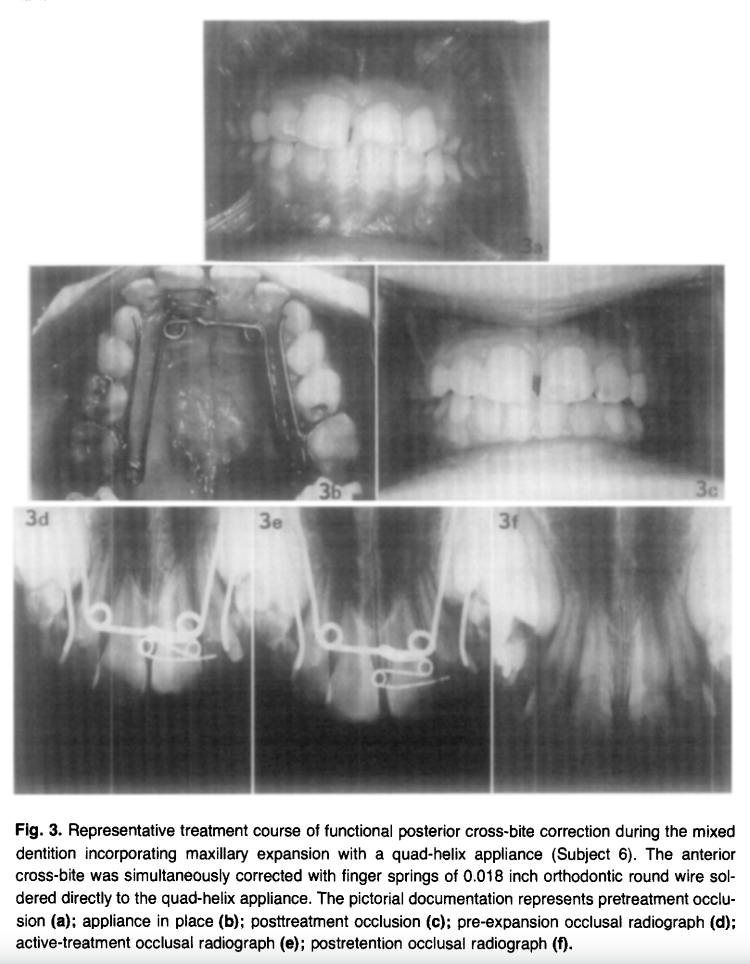

Every single subject (10/10) showed radiographic evidence of midpalatal suture opening on occlusal radiographs taken at 2 weeks of active treatment. The separation pattern was greatest anteriorly with a progressive posterior decrease — a classic sutural opening pattern. By end of retention, suture widening was no longer detectable radiographically, confirming bone fill-in.